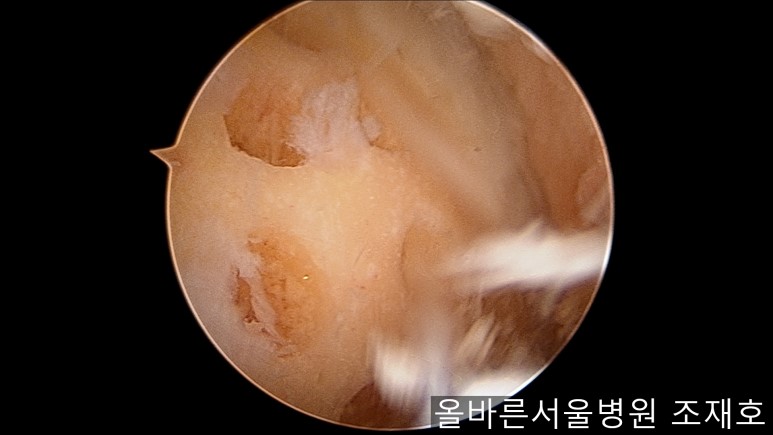

通过关节镜图像可看到:由于内侧股骨髁软骨损伤骨头已经显露出来。

胫骨上端的软骨损伤严重,也露出了骨头。

正是缺失软骨的部位碰到一起,引发剧烈疼痛,腿部逐渐变形。

与内侧对照,外侧的软骨及软骨板无损伤。